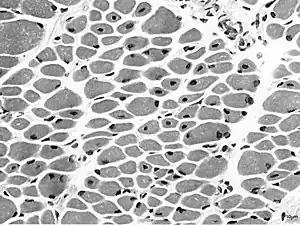

![]() | |

Muscle biopsy from the quadriceps taken at 3 months of age from a girl with X-linked centronuclear ("myotubular") myopathy due to a mutation in the myotubularin (MTM1) gene and extremely skewed X-inactivation (H&E stain, transverse section). Note marked variability in fibre size, moderate increase in connective tissue and numerous central nuclei. | |

On examination of muscle biopsy material, the nuclear material is located predominantly in the center of the muscle cells, and is described as having any "myotubular" or "centronuclear" appearance. In terms of describing the muscle biopsy itself, "myotubular" or "centronuclear” are almost synonymous, and both terms point to the similar cellular-appearance among MTM and CNM. Thus, pathologists and treating physicians use those terms almost interchangeably, although researchers and clinicians are increasingly distinguishing between those phrases.

In general, a clinical myopathy and a muscle biopsy showing a centronuclear (nucleus in the center of the muscle cell) appearance would indicate a centronuclear myopathy (CNM). The most commonly diagnosed CNM is myotubular myopathy (MTM). However, muscle biopsy analysis alone cannot reliably distinguish myotubular myopathy from other forms of centronuclear myopathies, and thus genetic testing is required.Diagnostic workup is often coordinated by a treating neurologist. In the United States, care is often coordinated through clinics affiliated with the Muscular Dystrophy Association.